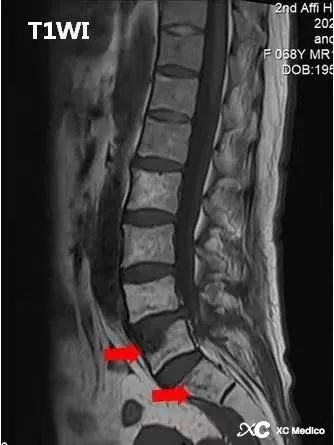

Примечание. Увеличенная MR: поясничная 4/5 выпуклость диска с остеофитами позвоночного обода, гипертрофия флавума лигаментума, небольшое сужение позвоночного канала и сжатие переднего края дурального мешка. Тело поясничного 5 позвонка ограничено вогнутым и может рассматриваться как полоски длинного T1 и T2 Wi Compression High Signal, а усиление наблюдается после усиления. Множественные участки аномального сигнала наблюдаются под конечными пластинами поясничного отдела 5 и сакральных 1 и под крестцовых суставов, с низким сигналом на T1WI и слегка высоким сигналом на T2WI, а усиление наблюдается при сканировании улучшения (красные стрелки). Было замечено утолщение мягких тканей на переднем крае крестцовых позвонков, а при усиленном сканировании наблюдалось усиление (синяя стрелка). Костные сигналы подвздошной кости, бедра, крестца и бедренной головы на обеих сторонах таза не показали никакой очевидной аномалии, и сигналы внутренних и внешних мышц таза были нормальными, с чистыми мышцами и нормальными разрывами суставов без признаков. расширения и сужения.